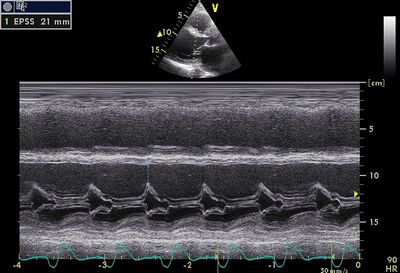

LVF slecht05.jpg

Dilated LV on PLAX

EPSS01.jpg

EPSS is a useful measurement to follow up DCM